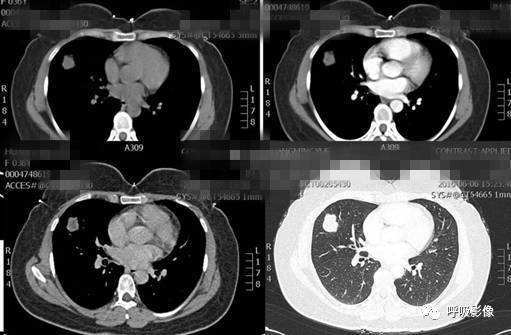

绒毛膜癌较侵袭性葡萄胎易发生转移。侵袭性葡萄胎肺部转移多以结节为主(图1),而绒毛膜癌肺部转移种类较多。

图1 女,31岁,侵袭性葡萄胎